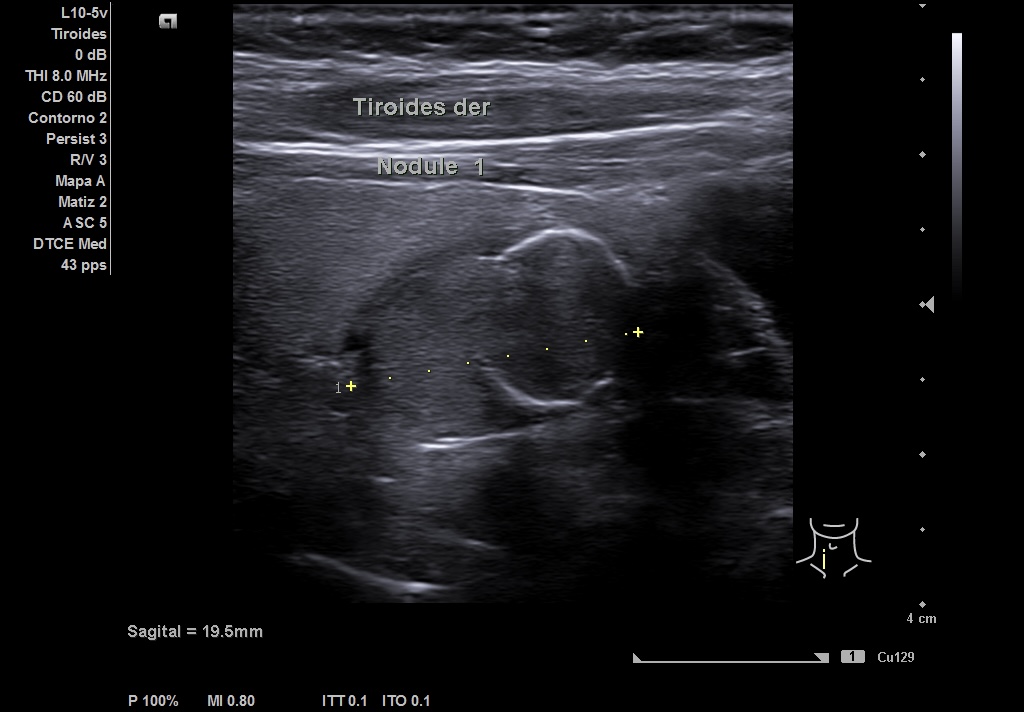

Se realiza ecografía en el Centro de Salud, en la que se objetiva en LTD un nódulo que impresiona de bilobulado, sólido, con una región caudal calcificada que no deja valorar su contenido y una parte superior isoecoica con alguna zona más hipoecoica. Diámetro antero-posterior (13 mm) mayor que el transversal (8 mm) y sagital (19 mm). Vascularización periférica. TIRADS 4-5.